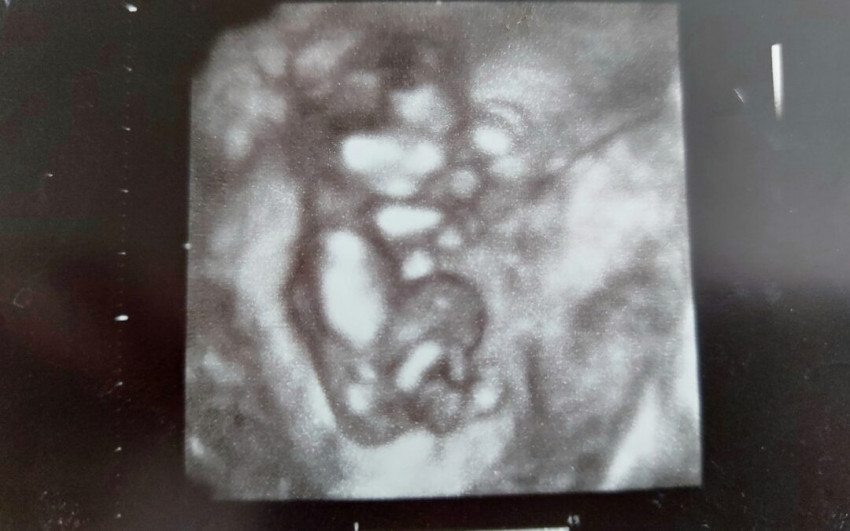

Borítókép: 13 hetes ultrahangkép, az utolsó fotónk Lelléről